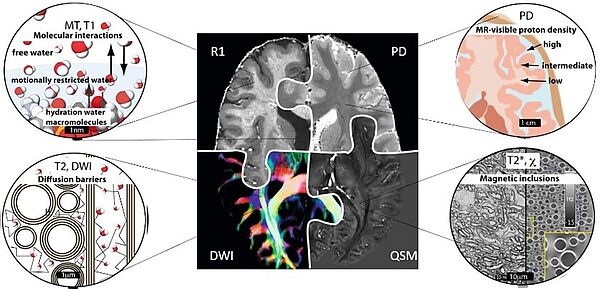

Microstructural basis of quantitative MRI parameters.

The central image shows four quantitative MRI maps, all reflecting tissue microstructure via different physical mechanisms. Clockwise from top left: longitudinal relaxation rate (R1=1/T1), proton density (PD), quantitative magnetic susceptibility map (QSM) and fractional anisotropy map obtained from DWI, color-coded with major anisotropy directions. Figure created by Evgeniya Kirilina and based on Weiskopf et al., Nat. Rev. Phys. (2021).